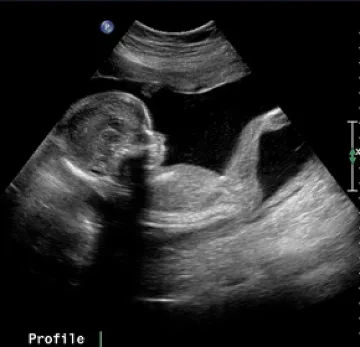

София. Приблизително 40 000 жени в Българи имат нужда от донорска яйцеклетка, за да станат майки. Те са на възраст между 25 и 45 години, но са със сер...